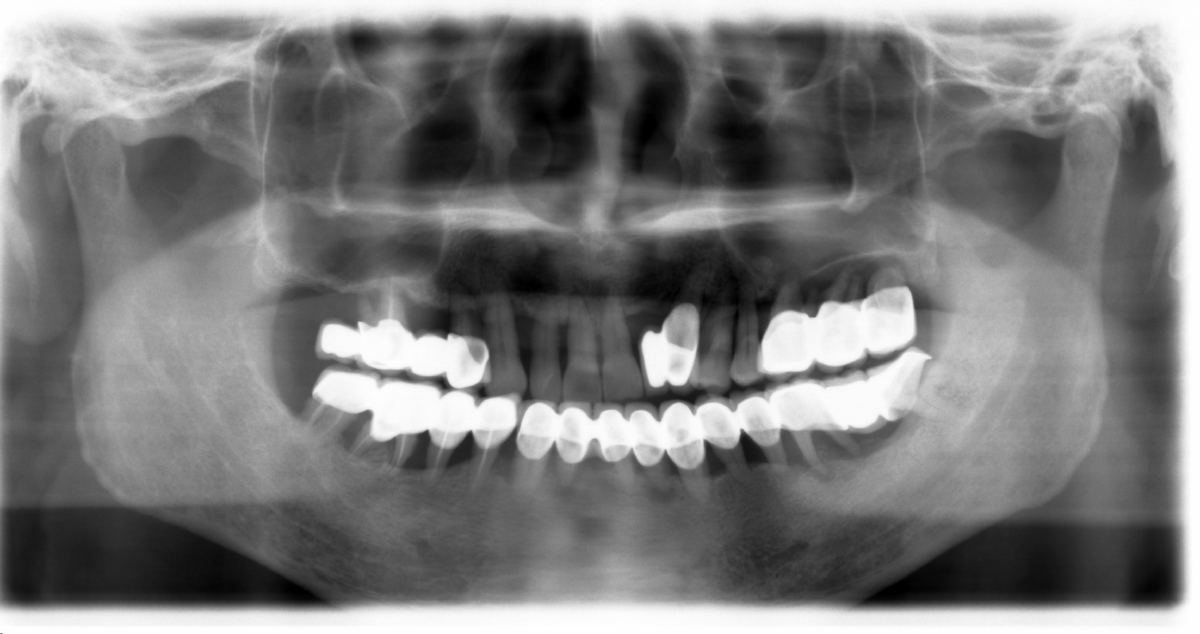

从口内照片上看,应该属于三类畸形下颌前突前牙反颌后牙近中错位,经过拔除左右下颌4进行矫正后的状态吧。

关于矫正,我是门外汉,只是平时工作中接触过这类问题而已。从全景片来看,似乎是会随着下颌智齿的萌出给前方牙列造成前推的力量,我建议请翁思恩以及其他有矫正经验的高手们谈谈高见,希望专家们能给一个理论性的指导。